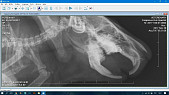

Вот рентгены недельной давности до подрезки зубов

Так же на нижней челюсти видно формирование как минимум двух периапикальных абсцессов. Требуется как минимум еще снимок в прямой проекции (вентро-дорсальной), чтобы посмотреть носовые ходы, раз есть хрипы, и определить степень перекоса челюстей, а так же посмотреть расположение корней верхних моляров, возможно, есть прорастание зубов в носовую полость.

Хорошо бы еще сделать снимок брюшной полости хотя бы в боковой проекции, посмотреть, нет ли газообразования в кишечнике или желудке. От этого будет зависеть назначение дополнительных препаратов в связи с жидким стулом. Возможно, потребуются антибиотики, стимуляторы перистальтики либо спазмолитики, а так же пробиотики.

На рентгене тимпания желудка, и содержимое в нем вызывает подозрение на волосяной ком (трихобезоар), хотя возможно это просто кормовые массы. Последите пожалуйста за регулярностью стула, при его задержке - сделайте рентген с контрастом (интервал дачи бария - 15 минут и 3 часа).

Ветеринар сказала, что абсцессов не видит, но завтра пощупает и если это не лимфатические узлы, то сказала если абсцессы маленькие - удалит без наркоза. Скажите пожалуйста, так правильно и видите ли вы абсцессы на новых снимках? Газового наркоза нигде нет. Спасибо за ответы!

Посмотрите пожалуйста есть ли на новых рентгеновских снимках абсцессы и где они точно находятся.

Прикладываем рентгены, спасибо!